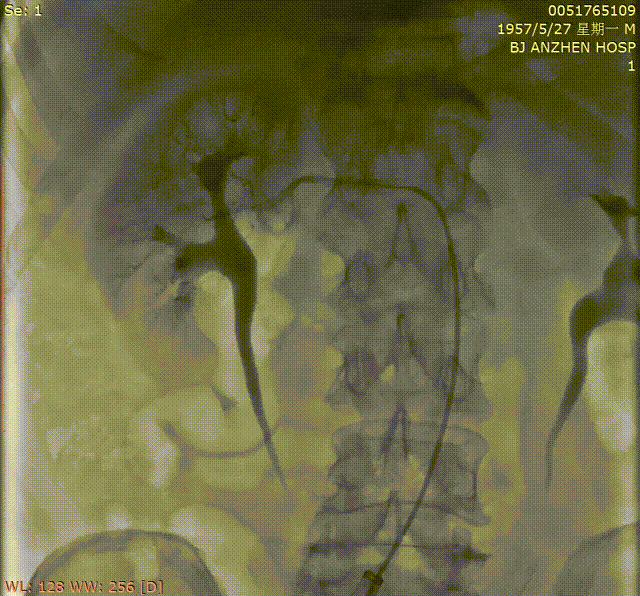

7.TAVR术后,行肾动脉造影,造影提示右侧肾动脉近端局限性狭窄,程度约80%。

肾动脉造影

8.沿导丝送入4mm*20mm球囊预扩张后,植入6*18mm支架一枚,再次造影提示支架位置良好,狭窄解除。

肾动脉支架植入